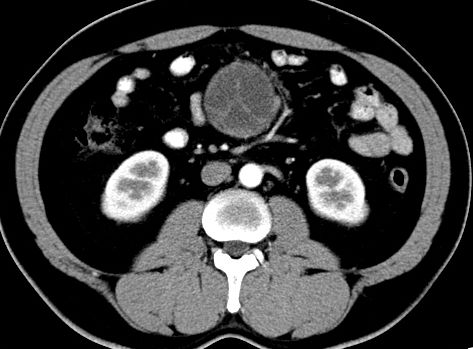

(腹腔)神经鞘瘤

男,48岁,间断性下腹不适1年。

手术探查

:距回盲部28厘米处肠系膜根部可见5*7cm左右包块,质中等硬度,活动度尚可,肝、胆、胰、脾肾未见明显异常。

病理

:(腹腔)

神经鞘瘤

,伴出血、坏死及囊性变,伴淋巴结反应性增生。

免疫组化结果

:sma(-), desmin(-), cd117(-), s-100(+++), nf(-),vimentin(+++).